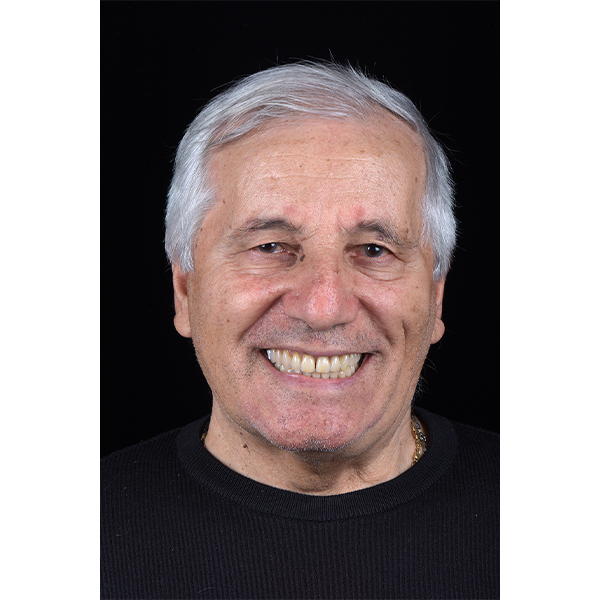

Après la mise en moufle et l'ébouillantage, les dents ont été repositionnées, conditionnées et des caractérisations blanchâtres, pourpres, orange clair, bleues et roses ont d'abord été réalisées au niveau du le bouclier labial. La base a ensuite été incrustée de résines pour prothèses de couleurs orange-rouge, rouge foncé, rouge clair, rose et rose foncé, et tous les polymères à chaud ont été pressés en une seule fois. Après le stockage sous pression, les prothèses finies ont été démouflées, finies et polies. La stratification anatomique tridimensionnelle de VITAPAN EXCELL en masse d'émail, de collet et de dentine avait un aspect absolument naturel dans l'anatomie muco-gingivale reproduite de la base prothétique. Le patient a pu s'habituer rapidement à sa nouvelle prothèse, notamment grâce à l'effet esthétique réussi. Après une courte phase d'adaptation et des corrections minimes dans l'environnement biodynamique, il s'est très bien débrouillé avec sa première restauration prothétique amovible complète et en était pleinement satisfait.